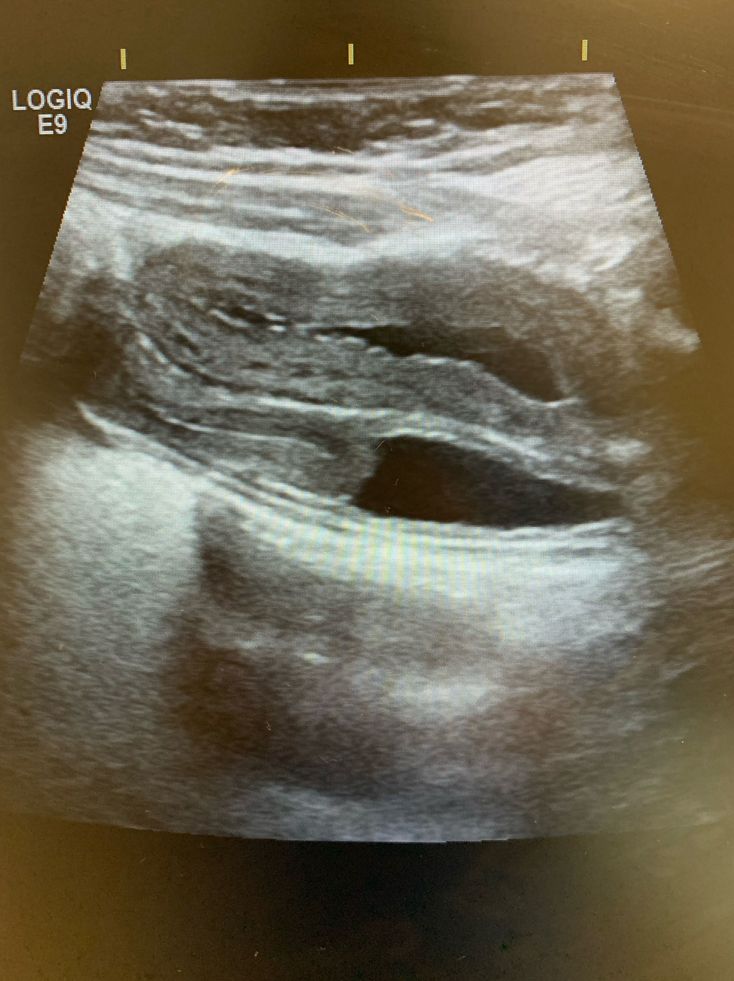

Can you tell what is the pathology here?

It was a KUB ultrasound for a four years old pt.

not sure but since it’s just a guess, hydronephrosis?